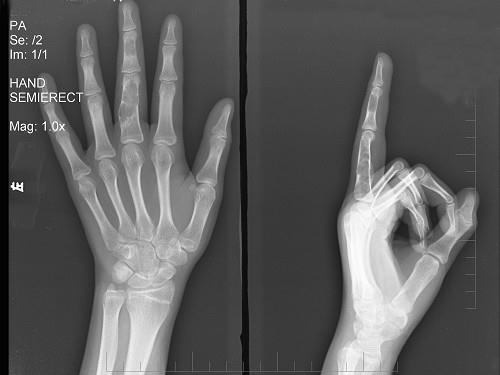

问题 男,15岁,左侧中指局部肿胀,无压痛,关节活动无明显异常,请结合所提供图像,选择最佳选项 ( )

选项 A、骨囊肿 B、动脉瘤样骨囊肿 C、内生软骨瘤 D、骨巨细胞瘤 E、骨质疏松

答案 C